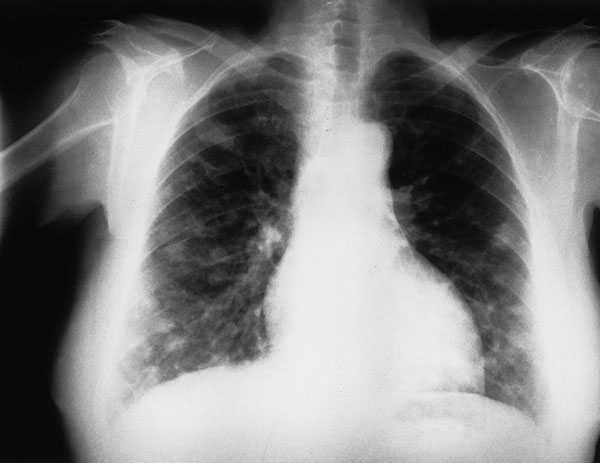

A la paciente se le realizó una radiografía posteroanterior de tórax (fig. 1), donde se observan nódulos múltiples bilaterales entre 1 y 2 cm de diámetro, presentando los nódulos bordes mal definidos.

Fig. 1.

Para decidir el régimen terapéutico adecuado tenemos que determinar no sólo el subtipo histológico o grado de malignidad, sino también cualificar el objeto de tratamiento, ya sea de carácter curativo o paliativo. Al mismo tiempo, no podemos perder de vista la posible presencia de otros procesos patológicos (cardíacos, renales, pulmonares) que pueden condicionar la toxicidad de la enfermedad. El pilar fundamental del tratamiento reside en la quimioterapia, que hoy en día ha conseguido buenos resultados en esta enfermedad. En la figura 2 se aprecia la desaparición de los nódulos múltiples bilaterales existentes tras la quimioterapia. La radioterapia desempeña un papel muy limitado en el tratamiento del linfoma no hodgkiniano.